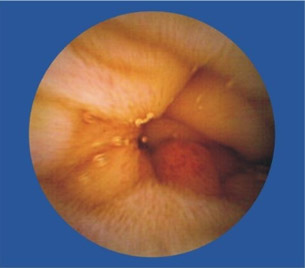

李女士,46岁。患有腹痛、腹泻、慢性肠炎等病史。肛门处轻度下坠感、偶有大便时肛门疼痛。口服胃肠药物,偶有缓解,但反复发作。经常规胃镜、肠镜、B超等检查未发现特殊病变,后到四川肛肠就诊车洪英主任结合腹痛部位考虑小肠病变可能,建议李女士做胶囊内镜检查,李女士在了解了胶囊内镜的检查原理及适应症、禁忌症后欣然接受此项检查。后经过胶囊内镜详细检查,确定了病变位置,然后李主任制定了详细的治疗方案,经过我院详细的治疗,李女士最后康复。

便血,去做检查,痔疮、胃镜、纤维结肠镜都做后,的出结论——小肠流血,但结肠镜够不着,还是看不见在具体位置。因此,也算是体验了下高科技,胶囊内镜。试过后真是感叹,这玩意儿真厉害!比普通药丸子稍大,一喝水下去了。自动掉头,自动拍照,自动传输。拉出来后找护士要了些消毒药水洗了下,细细观察。发现镜头口径有点小最多1mm,确实是高科技,这么小的东西,包括了拍照(可能是2个小时内的连续拍照),无线信号传输,方向姿势控制等等,厉害。

近日,67岁的陈爷爷因为便血导致严重贫血,胃镜、肠镜都做了却查不出病因。被转送到四川肛肠医院后,陈爷爷本来以为要再接受一次痛苦的内镜检查,没想到,医生给出的检查方式却是要他吞下一颗“胶囊”,同时穿上一件连着各种数据线的背心。很快,医生就发现陈爷爷的小肠上面存在一个不断出血的溃疡,经过手术,医生终于治好了陈爷爷的“怪病”。陈爷爷吞下的其实是一种叫“OMOM胶囊内镜”的检查仪器,主要用于小肠疾病的排查。